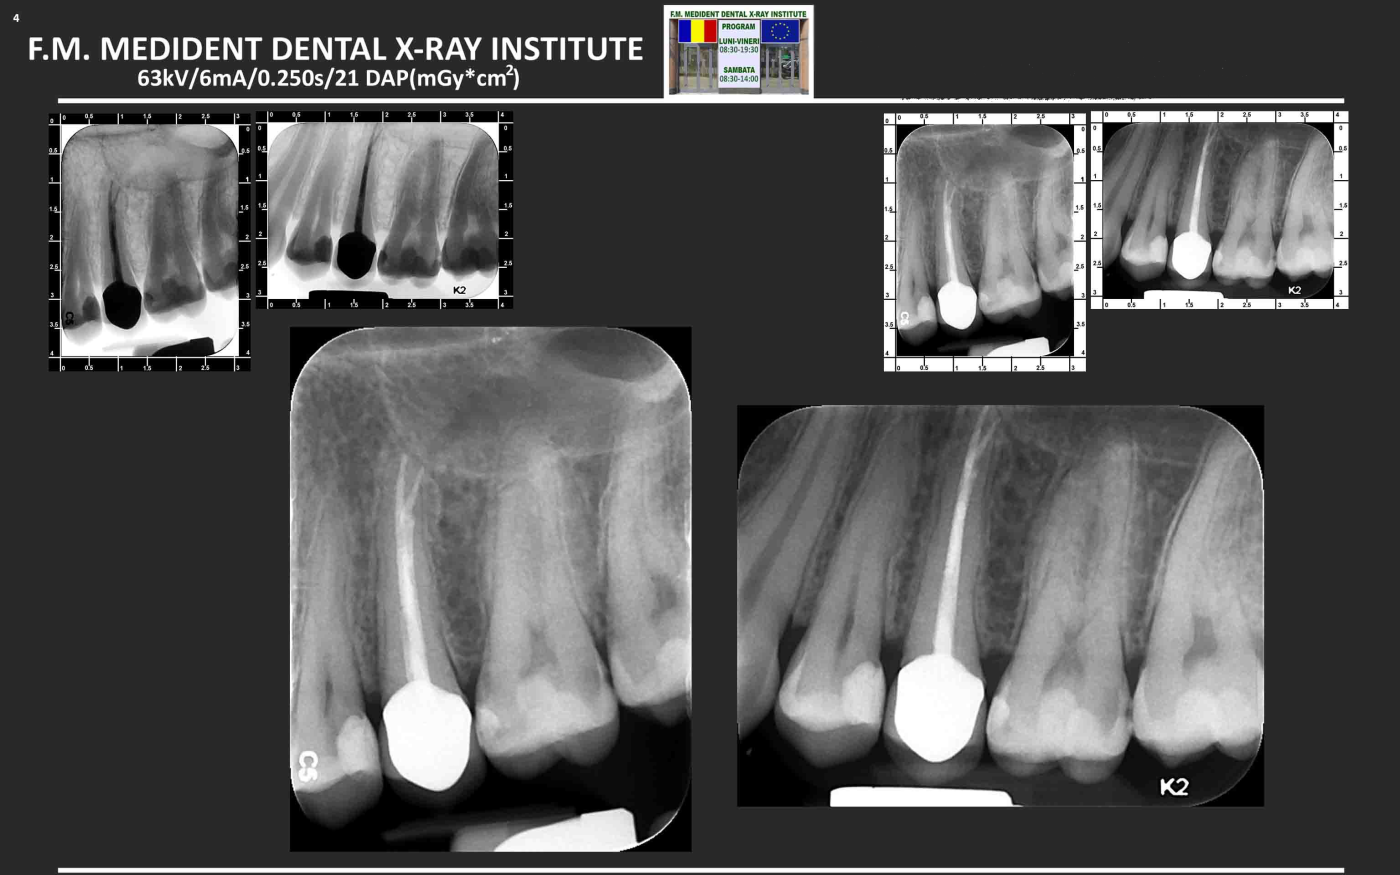

Aspectul radiologic dupa tratamentul de canal, inserarea pivotului si cimentarea coroanei definitive.